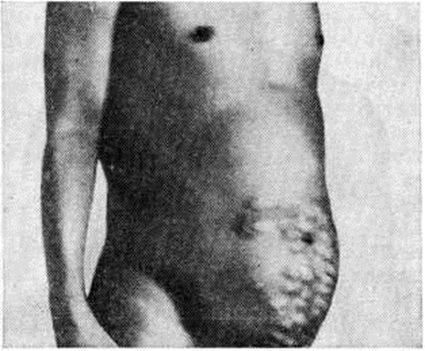

Нередко первым симптомом, выявляющим заболевание (особенно при внепечёночной форме Портальная гипертензия), является случайно обнаруженная увеличенная селезёнка или внезапно возникшее кровотечение из вен пищевода. Больные жалуются на общее недомогание, чувство тяжести в левом подреберье, иногда сопровождающееся болями и повышением температуры, метеоризм, увеличение живота. У больных с асцитом часто выявляются расширенные вены на передней брюшной стенке вокруг пупка (голова медузы) либо по направлению к грудной клетке или надлобковой области (рисунок 2) с характерным при аускультации шумом волчка над ними. Портокавальные анастомозы возникают при внутрипечёночном блоке портальной системы в результате функционирования пупочной вены и обозначаются как синдром Крювелье — Баумгартена (смотри полный свод знаний: Крювелье — Баумгартена синдром). При болезни Киари расширенные вены локализуются чаще по боковым стенкам живота (рисунок 3), на спине и нижних конечностях.

Рис. 2. | ||